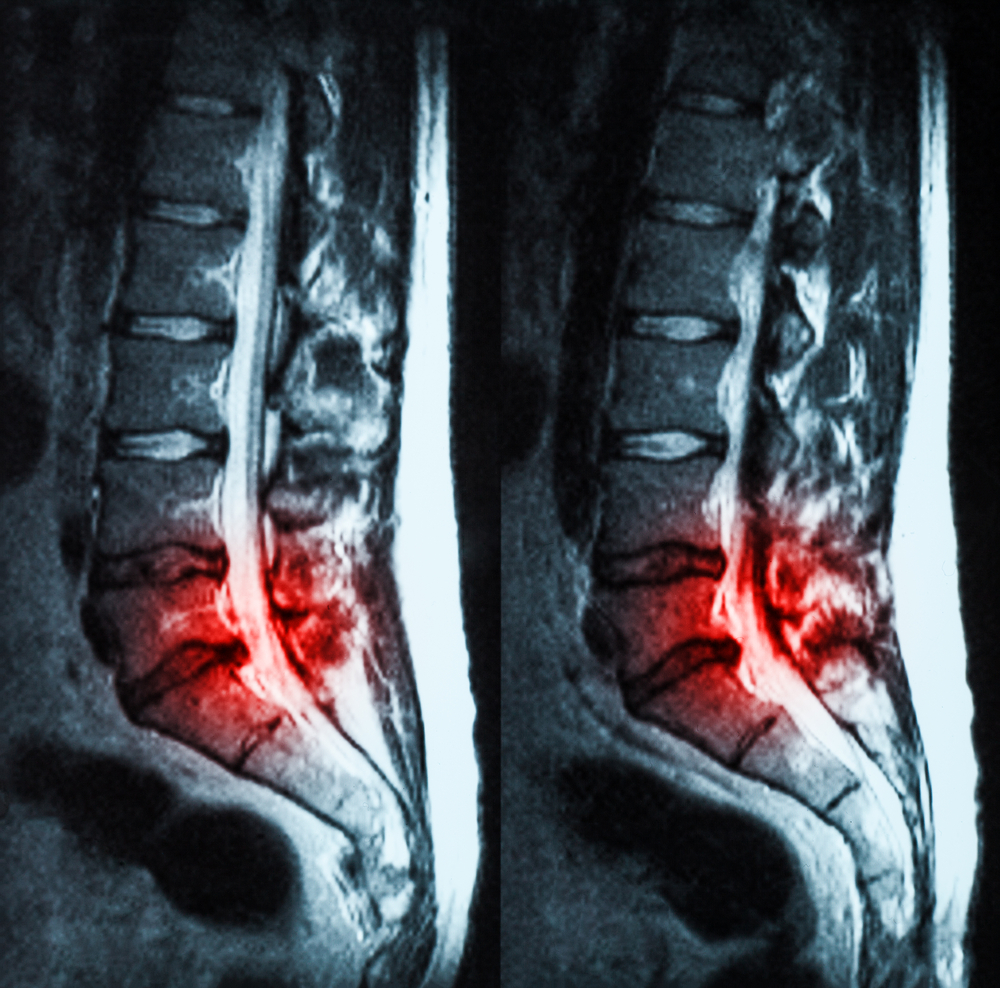

- Magnetic Resonance Imaging (MRI)

The goal is to establish accurate clinical correlation between anatomical narrowing and patient complaints.